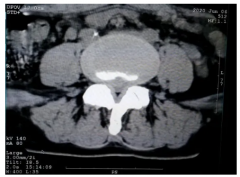

重庆送子鸟医院在诊断、治疗不孕不育疾病仪器方面也是不断优化检测设备及诊疗技术。同时在临床经验积累的基础上,讨论和研究各类疑难杂症,攻克了很多不孕不育疾病治疗难的问题!